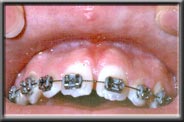

With the wear and tear of time, even normal attached gum can be worn away, generally from vigorous brushing. This often happens in people with naturally thin tissues, or when the tissues have been stretched during orthodontics. If there is still adequate attached gum to act as a barrier to the muscle, the treatment for recession is to ensure further damage isn't done when brushing. However, if the attached gum is worn to the point where it cannot resist the constant pull of the mucosa, recession will continue unless a new hard band of gum is placed. Unchecked, the recession can cause tooth loss as the bone recedes with the tissue and tooth support weakens.